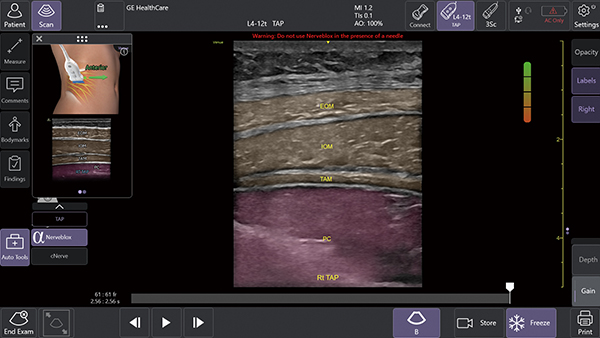

1. AIツール Nerveblox(ナーブブロックス)で神経ブロック手技を効果的にサポート

AIを用いて開発されたNervebloxは,区域麻酔に用いられる標準的な12種類の神経ブロック部位に対して,神経および周囲組織(筋肉・血管・骨・筋膜など)をリアルタイムに認識し,ハイライト表示する機能。

本機能は,画像クオリティを評価するQuality Meter,プローブの向きをガイドするOrientation表示,組織を色分けするカラーオーバーレイ,解剖構造名を示すアナトミカルラベル,理想的なプローブ位置を提示する模式図ガイド等を備え,走査者のエコー経験レベルに依存しない,より安定した神経描出をサポートする。

この機能により,麻酔科,救急科,集中治療科,整形外科など多くの診療科において,神経ブロック時の解剖学的構造の認識や視認性が高まることが期待され,よりスムーズな判断や手技をサポートする。

Nervebloxによる神経ブロックのサポート(中央)Anatomical Labeling:画像上に解剖学的ラベルを略語形式で表示 (右上)Quality Meter:表示画像の品質をリアルタイムで評価して色分け表示